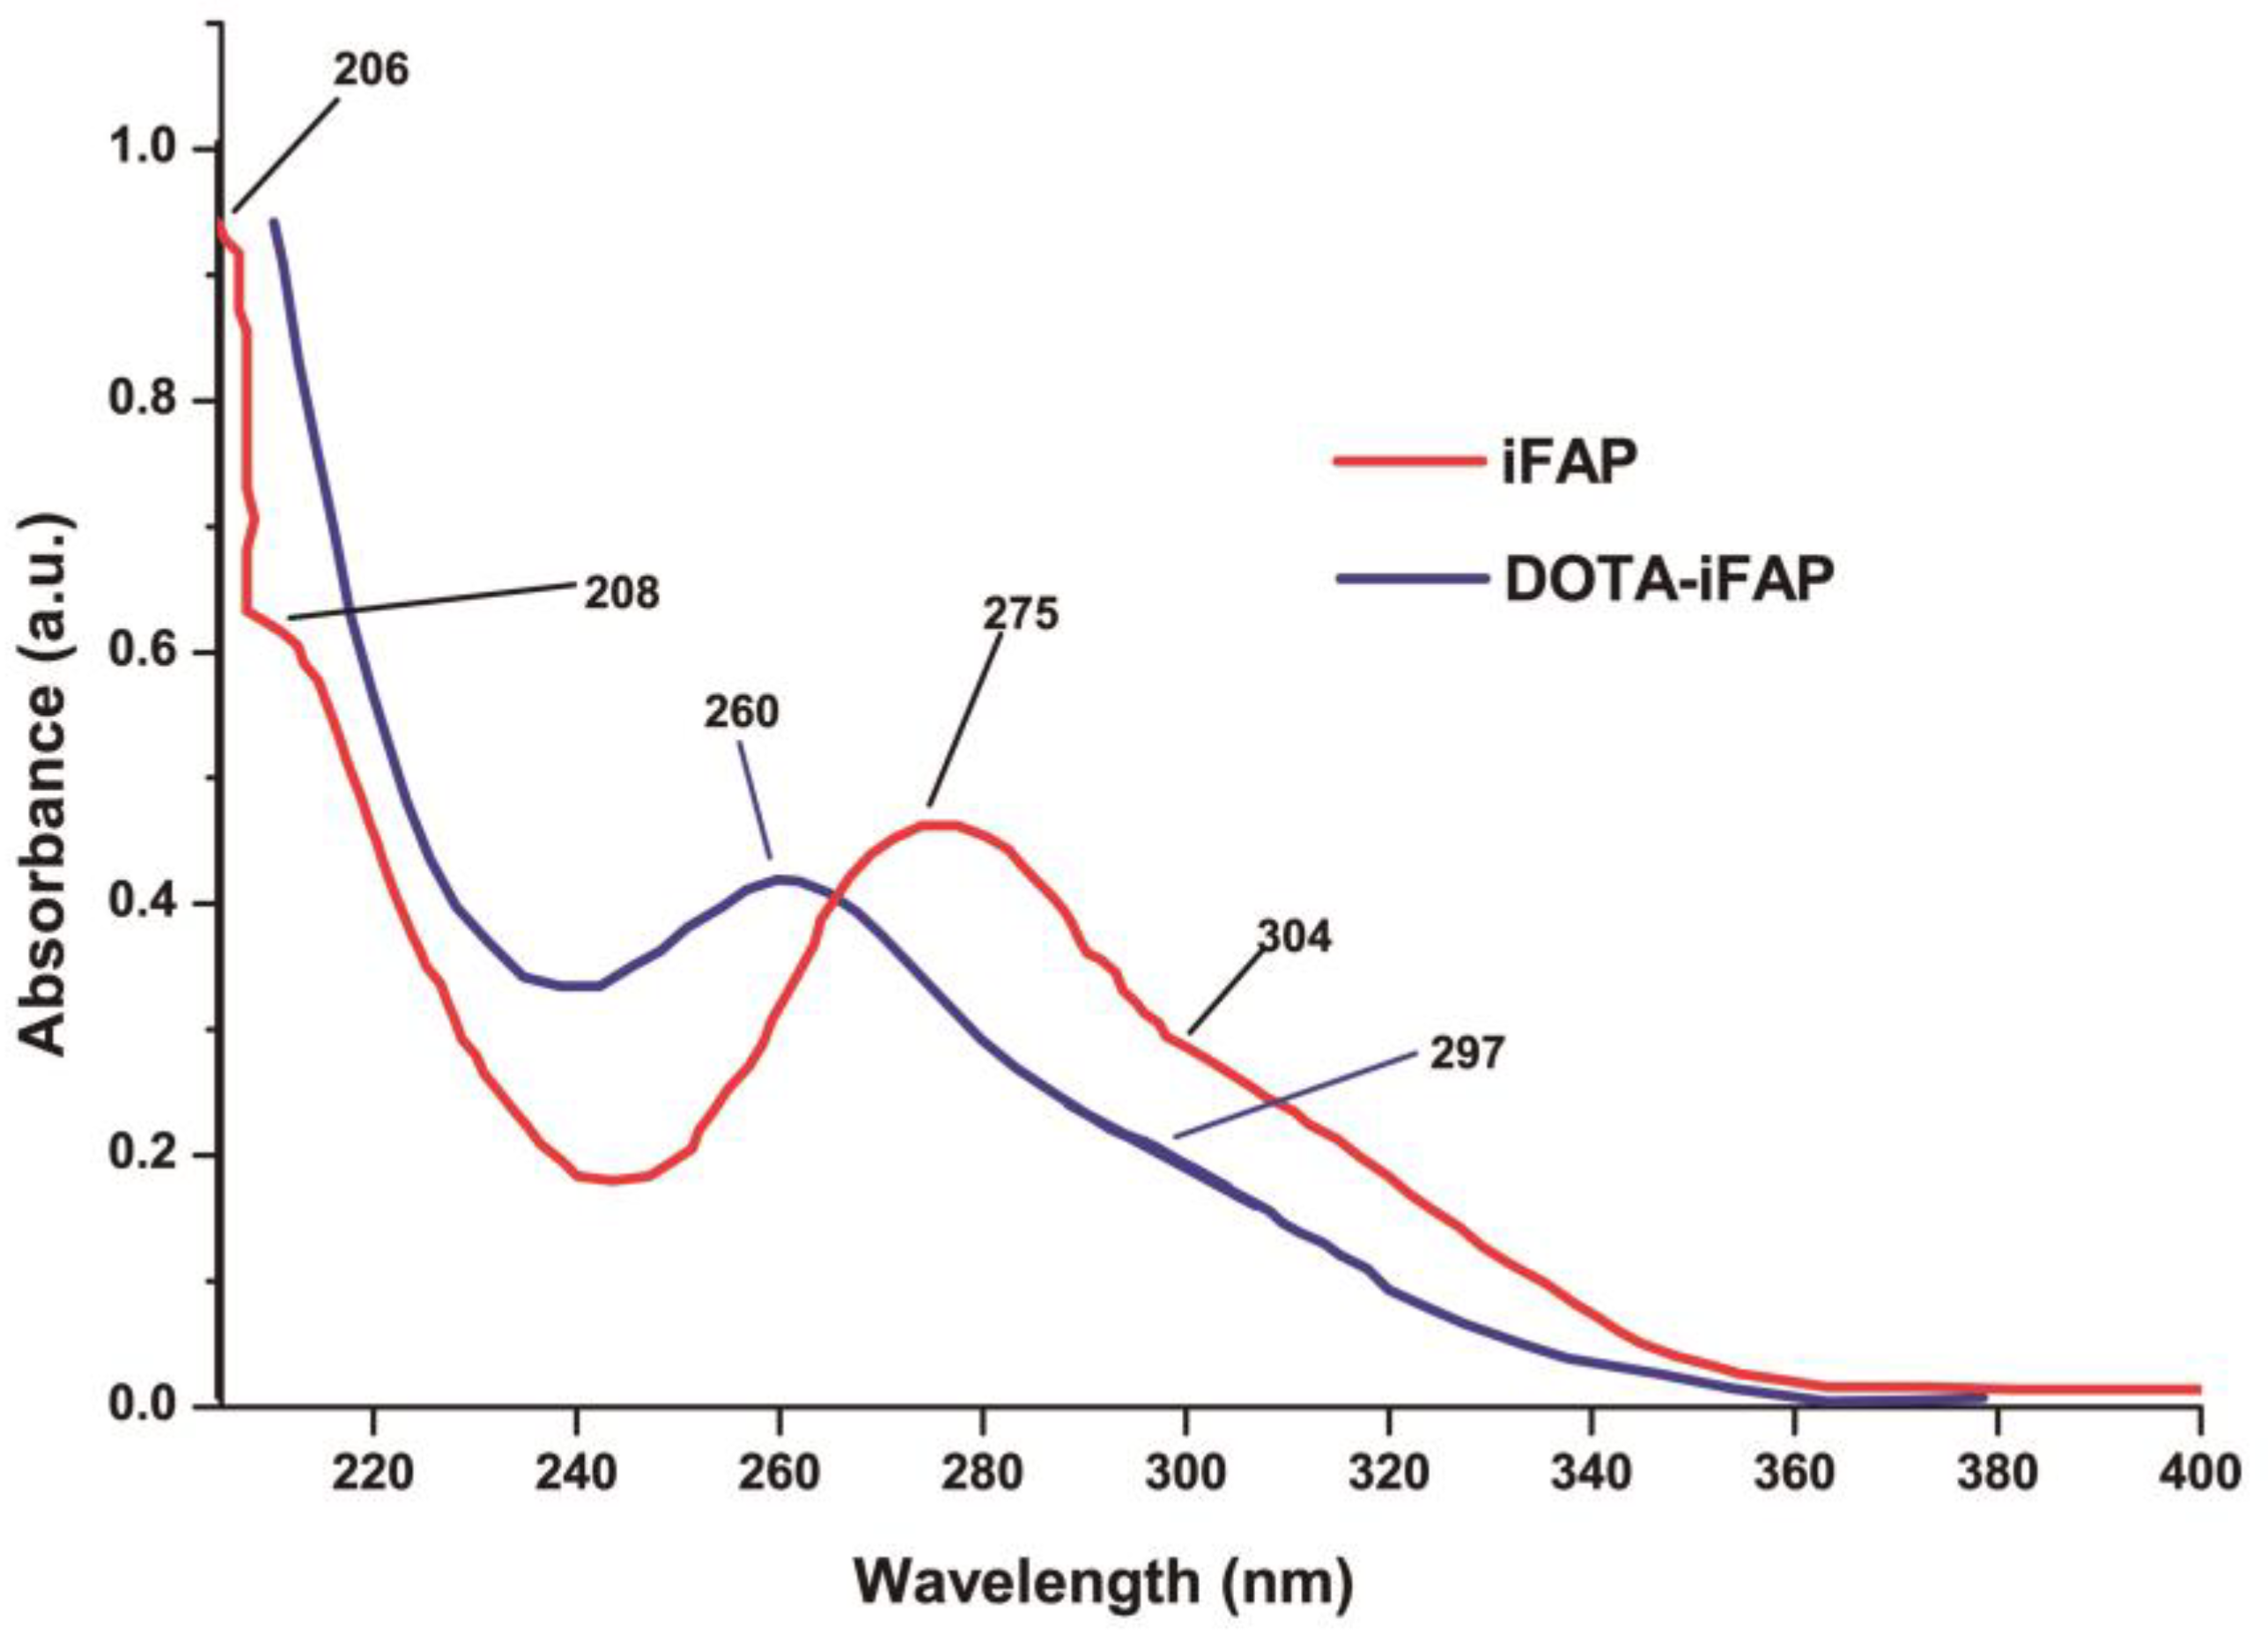

3.3. Chemical Evaluation

3.3.1. DOTA-iFAP